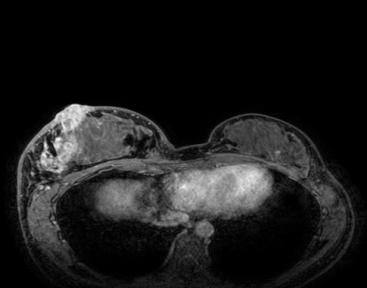

• 头颅MR(2025年10月18日):脑实质平扫增强未见明显异常。

图 2025年10月18日 头颅MR

②治疗18个月后,2025年10月18日颅脑MR对比2025年3月27日颅脑MR,患者脑转移灶消失,未见明显异常信号,达到CR,患者生活质量良好,药物耐受性好。

图 治疗18个月前(左列)后(右列)影像学疗效对比